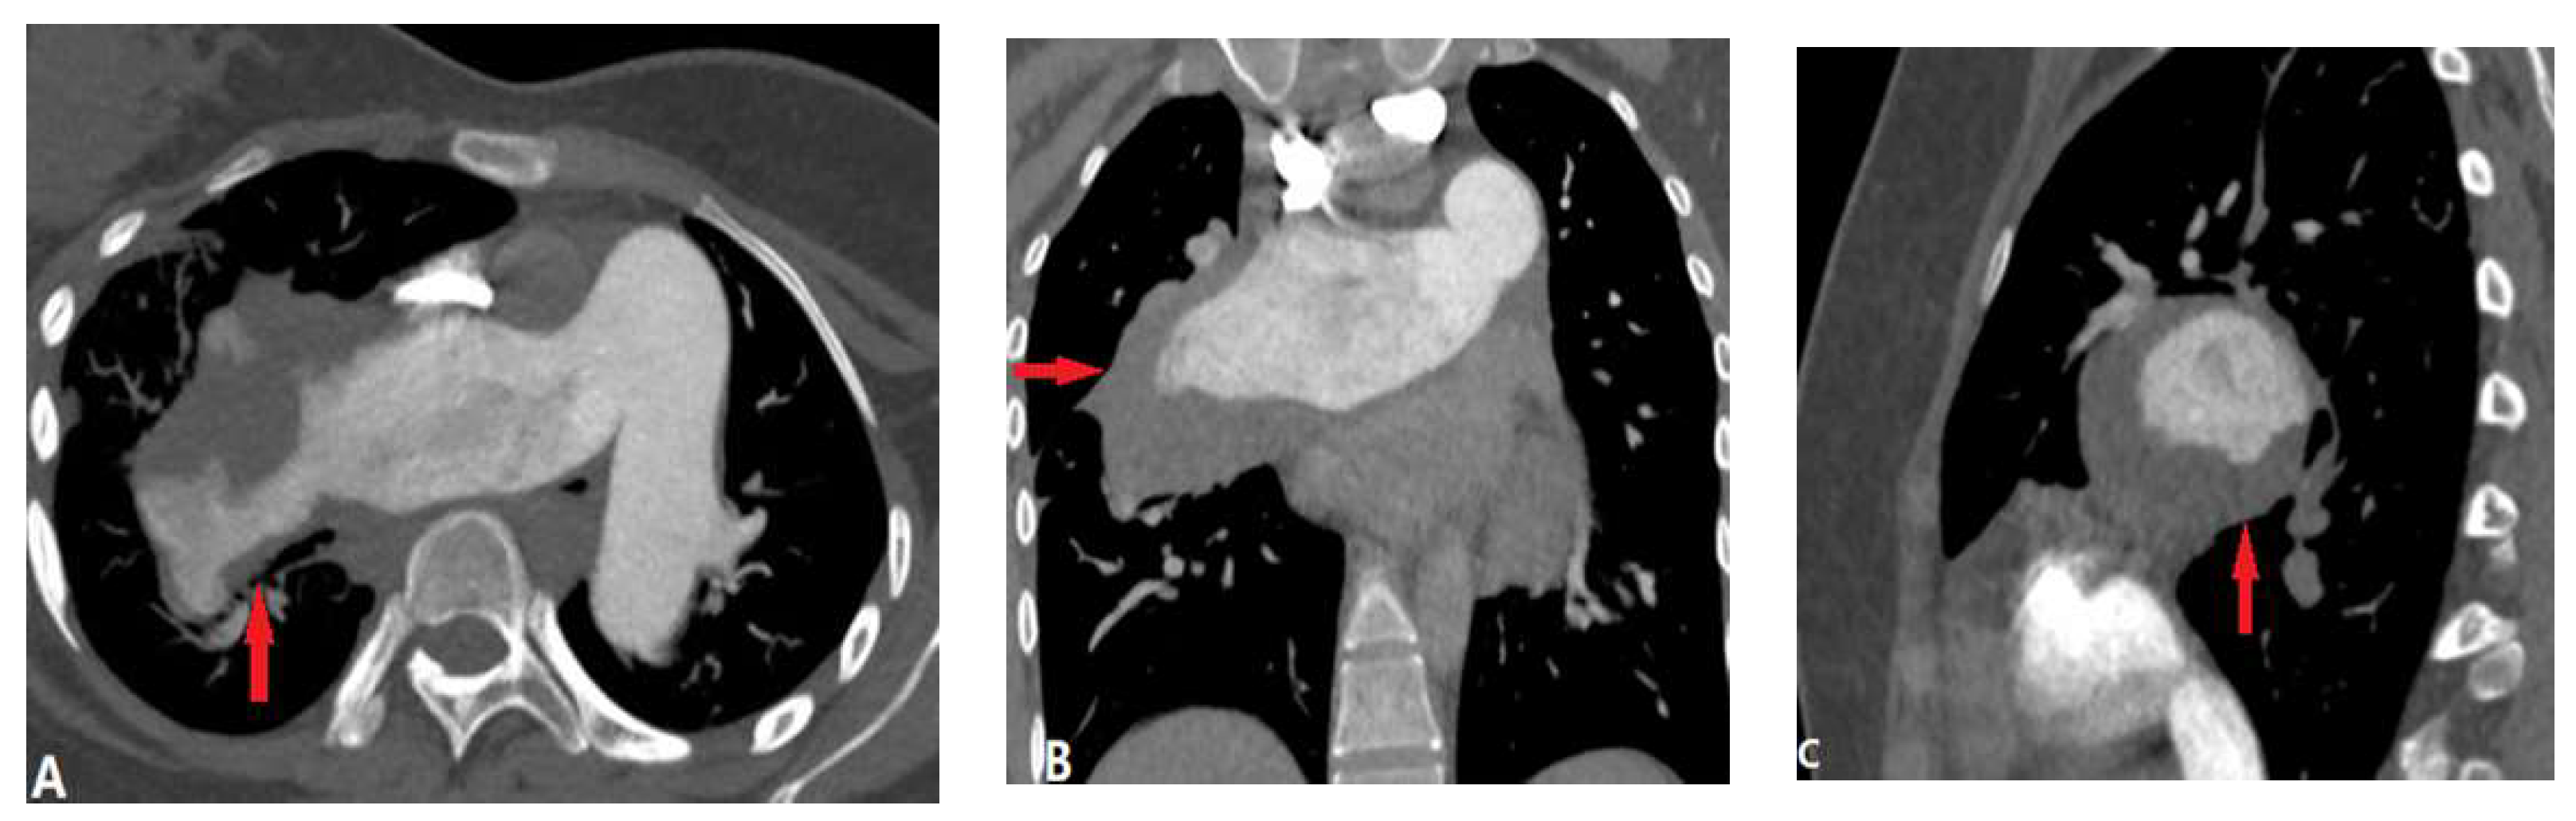

3.1.6. Pulmonary Artery Sarcoma

3.2. Vessel Wall Lesions